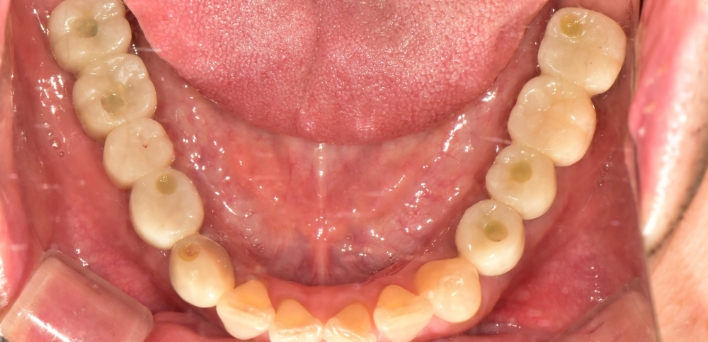

임플란트 : 손 ** 님 (50대)

After After

2020.02.30

환자 특징01무치악 상태

환자 특징02수년간 무치악으로 지내심

위, 아래 6개씩 식립

디지털 풀아치 임플란트